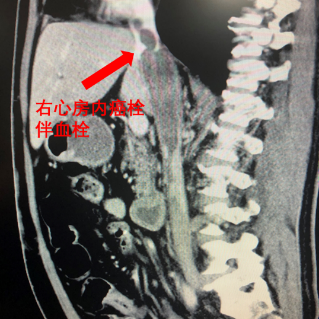

北醫三院泌尿外科主任、學科帶頭人張樹棟告訴“醫學界”,患者王先生此前被診斷為腎癌伴下腔靜脈癌栓,癌栓已從腎靜脈侵入下腔靜脈,甚至延伸至心臟附近。

患者影像資料/本文圖片皆來源於北醫三院

根據梅奧醫學中心(Mayo Clinic)的分級標準,王先生的病情被劃分為Mayo IV級,為該病的最高級別,手術風險極高。若實施手術,醫療團隊將面臨巨大的挑戰。